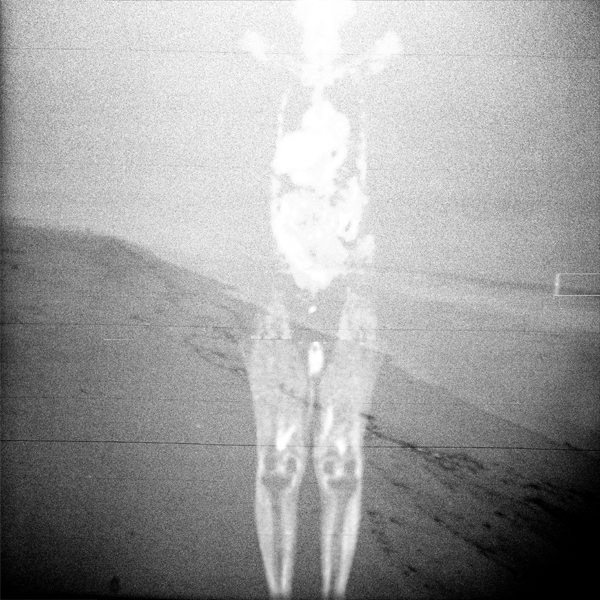

The physical or emotional turmoil that is inferred by the medical transparency of the human image is tempered by recognizable landscape. The natural world represents a place of peace and sanctuary.

These photographs illustrate how art and technology are intricately connected. While opposites in so many ways, they must co-exist. Without the landscape imagery, we are left with medical images, cold and impersonal. However, it’s the scientific and technological aspects that help breathe life into our human environment, leaving us with a true reflection of the human spirit, including a reminder of our shared strengths and vulnerabilities.